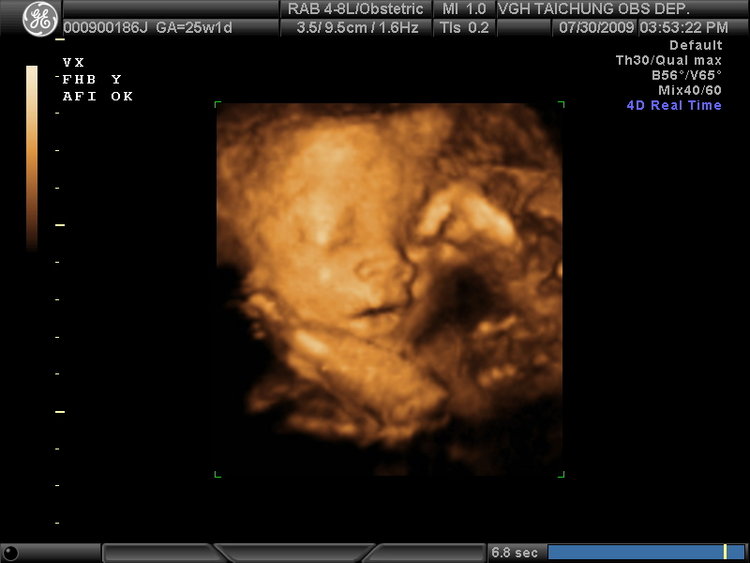

25週-高層次超音波-醫生說BB活潑過頭啦!

終於~第25週的高層次超音波於7/30完成啦^.^

分享一下照片囉>.<

圖一~BB打哈欠揉眼睛~

圖二~嘟嘴(老公說跟我一樣)